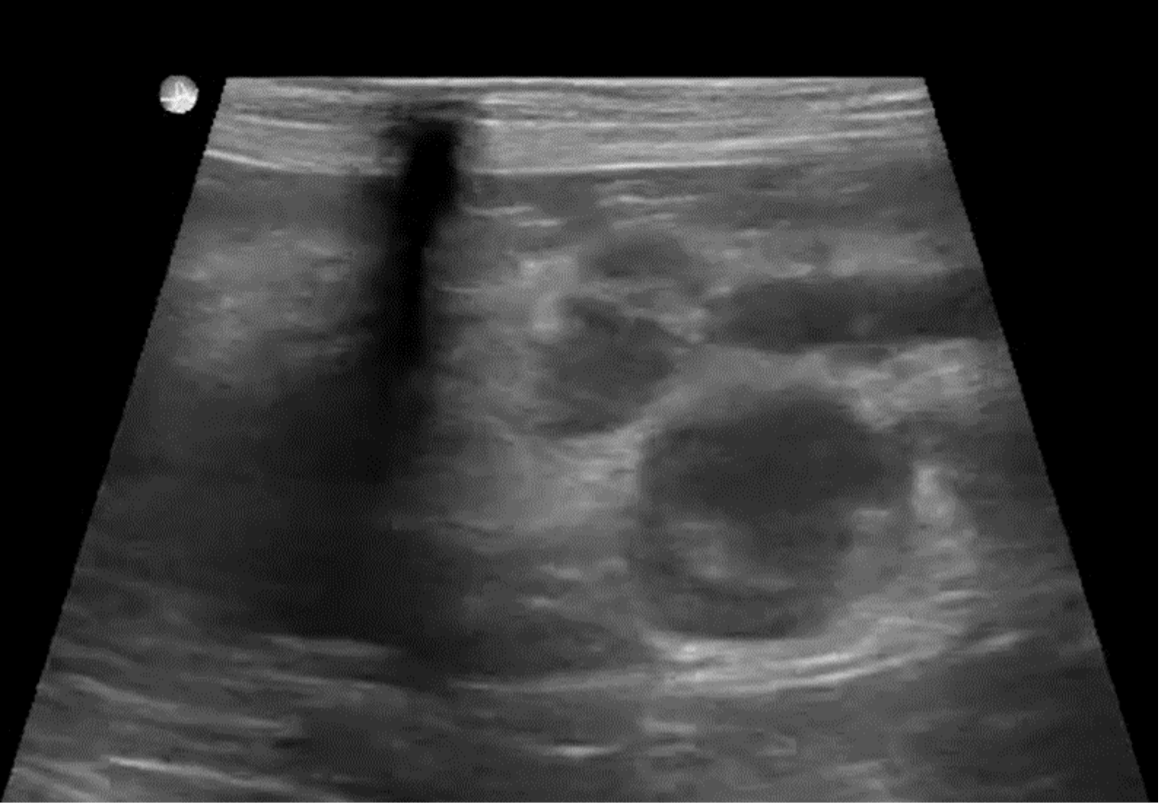

From mavink.com

Pancreatitis Dog Ultrasound Acupuncture Dog Pancreatitis An integrative approach focusing on both management. Studies have shown that acupuncture can improve gastrointestinal function, enhance gastric motility, and effectively treat abdominal. Acute inflammation of the pancreas is associated with abdominal pain. When treating pancreatitis, both allopathic and alternative therapies are available, although emphasis should be on the latter. Dogs with diabetes, kidney or liver failure, pancreatitis, cushing’s disease,. Acupuncture Dog Pancreatitis.

From blog.oncurapartners.com

Ultrasound Characteristics of Canine Pancreatitis Acupuncture Dog Pancreatitis Dogs with diabetes, kidney or liver failure, pancreatitis, cushing’s disease, and addison’s disease have experienced a decrease in nausea. Acupuncture is beneficial for the treatment gi hypermotility and diarrhea whether it is due to a viral/bacterial gastroenteritis such as parvovirus. An integrative approach focusing on both management. When treating pancreatitis, both allopathic and alternative therapies are available, although emphasis should. Acupuncture Dog Pancreatitis.

Ultrasound Characteristics of Canine Pancreatitis Acupuncture Dog Pancreatitis Studies have shown that acupuncture can improve gastrointestinal function, enhance gastric motility, and effectively treat abdominal. Acute inflammation of the pancreas is associated with abdominal pain. Acupuncture is beneficial for the treatment gi hypermotility and diarrhea whether it is due to a viral/bacterial gastroenteritis such as parvovirus. Dogs with diabetes, kidney or liver failure, pancreatitis, cushing’s disease, and addison’s disease. Acupuncture Dog Pancreatitis.